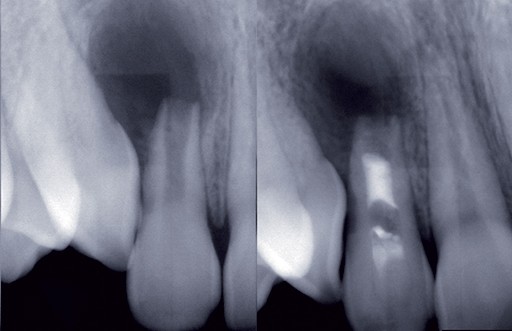

Alors que le coiffage pulpaire est considéré comme une approche régénérative du complexe « odontoblasto-dentinaire », et donc très limité, le principe de régénération intra-canalaire engage un processus de régénération plus large et finalement plus complexe.

Bien que le traitement endodontiqueconventionnel soit considérécomme une technique validée et au pronostic acceptable, il apparaît que la régénération de novo d’un tissupulpaire ou d’un tissu conjonctifà l’intérieur du canal présente un certain nombre d’avantages en comparaison avec l’obturation à la gutta percha scellée qui, bien que correctement effectuée, reste instable et susceptible à la réinfection dans le temps.

Les premières tentatives de régénération ont eu lieu dans les années 1960 [1]. L’objectif était alors de remplir le canal concerné avec un caillot sanguin issu d’un saignement péri-apical. Les résultats obtenus étaient encourageants, mais le fait que le tissu régénéré à l’intérieur du canal était plus proche d’un tissu parodontal que pulpaire a fait avorter les investigations sur le sujet, laissant place au développement des techniques instrumentales et oubliant la biologie comme moyen thérapeutique. Depuis 2001, date de la publication du premier cas clinique de « régénération » [2] l’idée de régénérer un tissu au sein d’un canal infecté a suscité de nouveau l’intérêt des scientifiques et des cliniciens et le concept a donné naissance à un domaine de recherche spécifique et particulièrement actif en endodontie. La multiplication des rapports de cas publiés dans la littérature tend à démontrer l’intérêt clinique de ces thérapeutiques, mais la variabilité des résultats obtenus nous incite dorénavant à nous intéresser à la nature du tissu biologique formé dans le canal et…